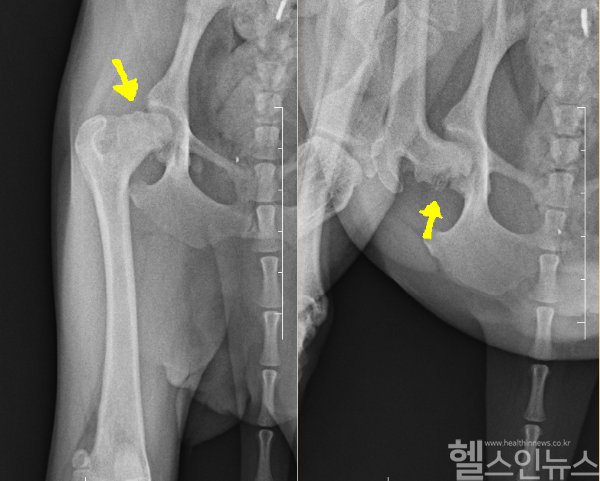

대퇴골은 허벅지에 위치한 가장 큰 뼈인데 상단 끝 머리쪽에 있는 부위를 대퇴골두라고 한다. 대퇴골두는 골반뼈의 관골구에 딱 맞게 들어가 고관절의 자유로운 운동에서의 중심 역할을 하며, 반려동물의 체중을 후지로 전달하는 역할을 한다. 하지만 유전적 요인이나 혈관의 이상으로 인해 대퇴골두로 가는 혈액 공급이 차단되면, 뼈세포가 죽어 결국 괴사에 이르게 된다. 이러한 질환을 대퇴골두허혈성괴사 또는 대퇴골두무혈성괴사라고 부른다.

진단을 받으면 내과적인 치료보다는 외과적 수술이 필요한 경우가 많다. 가장 많이 시행되는 수술 방법은 괴사된 대퇴골두를 제거하여 고관절의 근본적인 통증 원인을 없애는 방법이다. 대퇴골두허혈성괴사는 치료가 늦어질수록 대퇴근육량이 줄어들어 정상 기능 회복에 더 많은 시간을 요구한다. 따라서 반드시 반려견이나 반려묘 보행에 이상이 발견되면 바로 동물병원에 찾아 진단을 받아보는 것이 좋다.